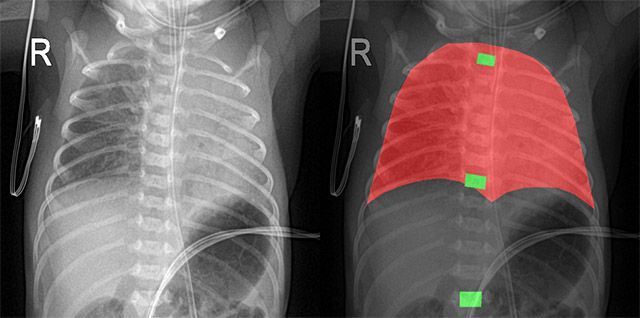

고려대학교 안산병원 소아청소년과 최병민 교수 연구팀은 딥러닝 기반 nnU-Net 모델을 활용해 신생아 흉부 X-ray 영상에서 주요 기준점인 흉추 T1, T7, T12를 자동으로 분할·표시하는 시스템을 개발했다. 이번 연구에는 코어라인소프트 연구진이 공동으로 참여했다.

연구팀은 국내 10개 대학병원에서 수집한 약 1만4000건의 신생아 흉부 X-ray 영상을 학습·검증에 활용했다. 그 결과 DSC threshold 0.50 또는 0.60 기준에서 흉추 위치 식별 정확도가 90% 이상이었으며, 다양한 촬영 환경에서도 일관된 성능을 보였다.

이번 연구는 카테터나 기관삽관 튜브의 위치를 직접 판독하는 것이 아니라, 해당 위치를 평가하기 위한 해부학적 기준점을 자동으로 제시하는 데 초점을 맞췄다. 기존에는 의료진이 흉추 위치를 기준으로 기구의 적정 위치를 판단해 왔으며, 이 과정은 경험과 육안 판독에 크게 의존하는 영역으로 꼽힌다.